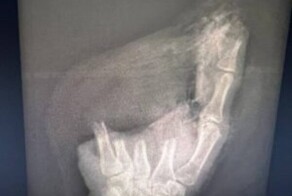

После травматологического этапа, во время которого были соединены кости, сухожилия, сгибатели и разгибатели пальца, врачи провели микрохирургический, наиболее сложный, во время которого сшиваются нервы и сосуды.

"Реплантация прошла успешно, мальчику, можно сказать, повезло - механизм травмы был "гильотинным", без размозжения, поэтому у нас была возможность сохранить максимальную длину пальца", - рассказал микрохирург Павел Гончарук.